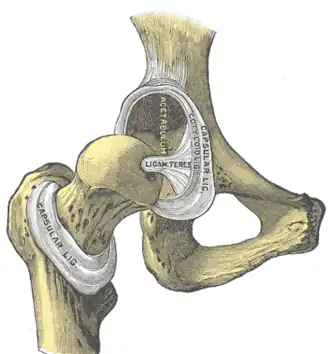

The hip joint is reinforced by four ligaments, of which three are extracapsular and one intracapsular.

The extracapsular ligaments are the iliofemoral, ischiofemoral, and pubofemoral ligaments attached to the bones of the pelvis (the ilium, ischium, and pubis respectively). All three strengthen the capsule and prevent an excessive range of movement in the joint. Of these, the Y-shaped and twisted iliofemoral ligament is the strongest ligament in the human body. It has a tensile strength of 350 kg.[24] Iliofemoral ligament is a thickening of the anterior capsule extending from anterior inferior iliac spine to intertrochanteric line.[7] Ischiofemoral ligament is the thickening of posterior capsule of the hip and pubofemoral ligament is the thickening of the inferior capsule.[7] In the upright position, iliofemoral ligament prevents the trunk from falling backward without the need for muscular activity, thus preventing excessive hyperextension. In the sitting position, it becomes relaxed, thus permitting the pelvis to tilt backward into its sitting position. Ischiofemoral prevents excessive extension and the pubofemoral ligament prevents excess abduction and extension.[26]

The zona orbicularis, which lies like a collar around the most narrow part of the femoral neck, is covered by the other ligaments which partly radiate into it. The zona orbicularis acts like a buttonhole on the femoral head and assists in maintaining the contact in the joint.[24] All three ligaments become taut when the joint is extended - this stabilises the joint, and reduces the energy demand of muscles when standing.[27]

The intracapsular ligament, the ligamentum teres, is attached to a depression in the acetabulum (the acetabular notch) and a depression on the femoral head (the fovea of the head). It is only stretched when the hip is dislocated, and may then prevent further displacement.[24] It is not that important as a ligament but can often be vitally important as a conduit of a small artery to the head of the femur, that is, the foveal artery.[28] This artery is not present in everyone but can become the only blood supply to the bone in the head of the femur when the neck of the femur is fractured or disrupted by injury in childhood.[29]